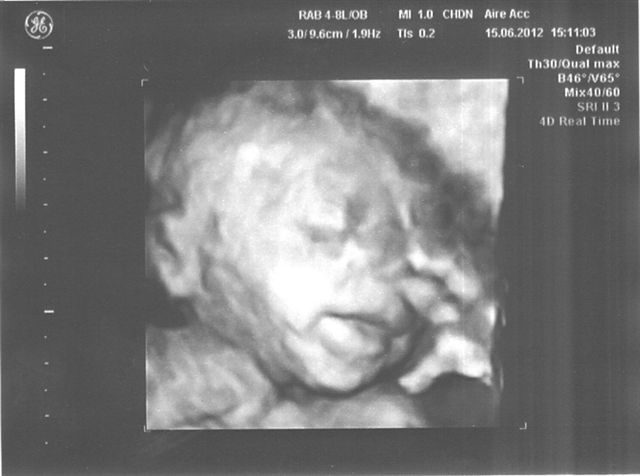

Mein Traum ist wahr geworden! [Vorstellung]